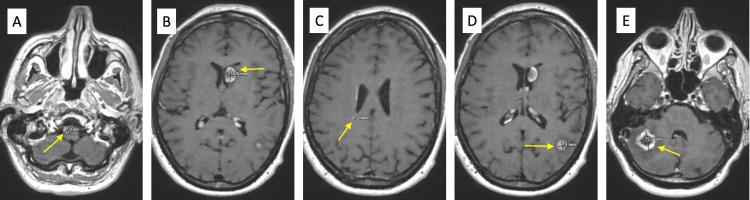

Sclerosing epithelioid fibrosarcoma (SEF) is an extremely rare subtype of sarcoma that appears histologically low-grade yet usually has a clinically aggressive course with a high rate of local recurrence and distant metastasis. However, these recurrences and metastases often occur years after initial treatment. Metastases can be to the lung as well as extra-pulmonary sites. In this case report, we discuss a patient who developed SEF in the deep soft tissue with metastases. This patient underwent checkpoint inhibitor therapy, with disease response. Thus, SEF is a sarcoma subtype with a unique tumor biology, and immunotherapy may be a promising avenue for treatment.

硬化性上皮样纤维肉瘤(SEF)是一种极其罕见的肉瘤亚型,其组织学表现为低级别,但临床过程通常具有侵袭性,局部复发率和远处转移率较高。然而,这些复发和转移往往在初始治疗数年之后才会出现。转移部位可以是肺部以及肺外部位。在本病例报告中,我们讨论了一名在深部软组织发生SEF并伴有转移的患者。该患者接受了检查点抑制剂治疗,并出现了疾病反应。因此,SEF是一种具有独特肿瘤生物学特性的肉瘤亚型,免疫疗法可能是一种有前景的治疗途径。